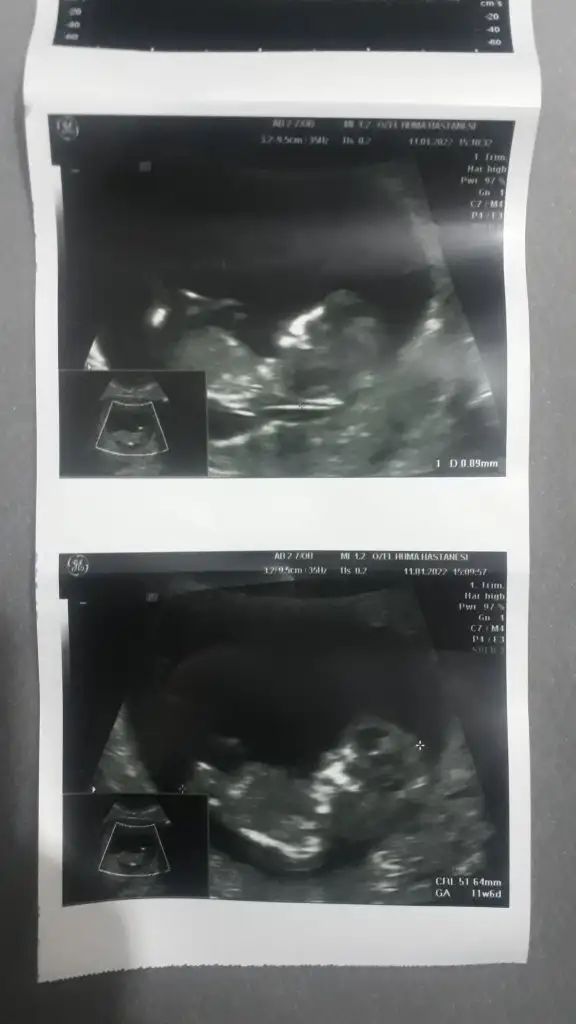

Kiz görünüyorMerhabalar 12+0 haftaligim cinsiyet tahmini yaparmisiniz isminizi temmuz annelerinden duydumIkra meyra

Erkek gibiCinsiyet ne bakabilir misiniz?Ikra meyra

Emin değilim ama sanki erkek gibi başka USG varsa paylaşınMerhaba benimkisi 12 haftalık tam. Bakar mısın lütfen. Doktor 10. Haftada erkeğe benzetti ama bugün de kız gibi dedi :)

Erkek gibi sankiBuna da bakar mısınız 12+6Ikra meyra

Çok teşekkür ederim vakit ayırıp baktığınız için 1 ay sonrasına gün attı doktorum kesinlesir kesinlesmez paylasicamKiz görünüyor